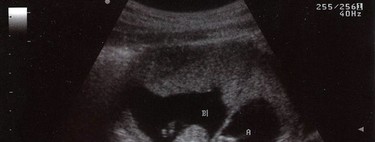

¿Cuánto dura un embarazo múltiple?

Un embarazo en el que se esperan dos bebés o más tiene un riesgo más elevado de terminar en parto prematuro. A diferencia de aquellos en los que solamente se espera un bebé y lo ideal es llegar a las 40 semanas, en un embarazo múltiple la duración es menor.

Por lo regular, en el caso de un embarazo gemelar donde todo transcurra bien la duración media es de 37 semanas, una duración muy ideal para dar a luz de acuerdo con estudios, mientras que en el de trillizos la duración del embarazo puede acortarse aún más, siendo el promedio 34 semanas, y en el caso de cuatrillizos de 32 semanas.